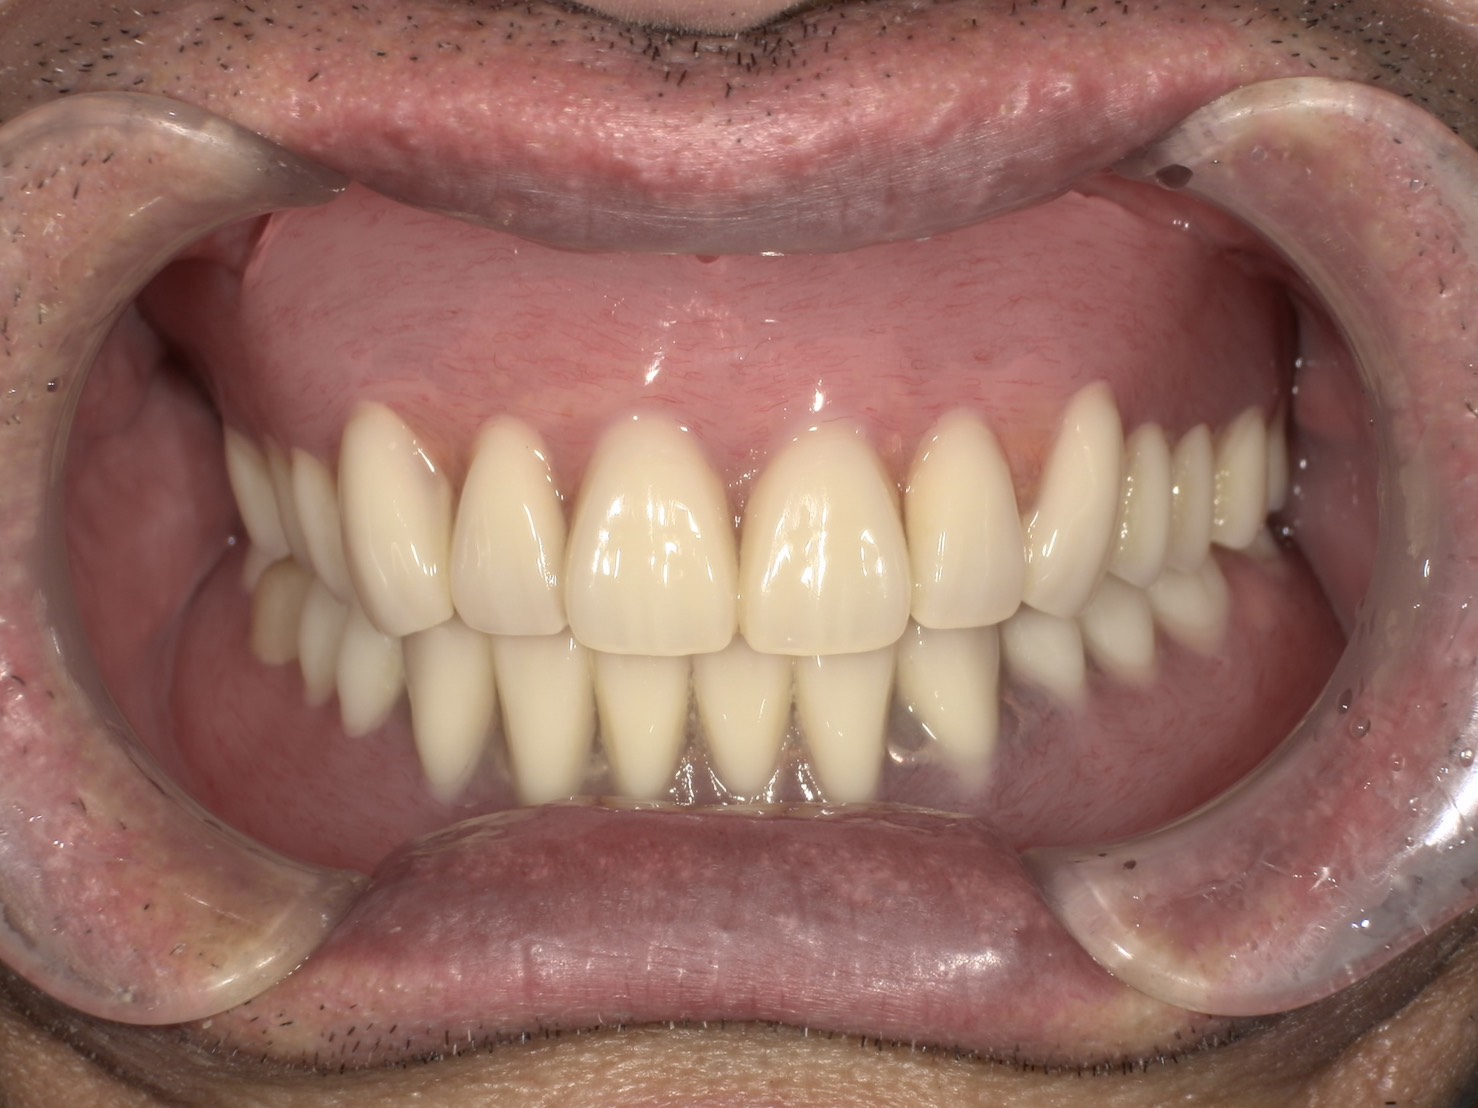

装着してもらった状態です

安定感が非常に高く、本人曰く

『ほとんどの物は咬める』とのことでした。

個人差はあると思いますが、

おせんべいも問題なく咬めるそうです。

ちなみにこの方は総入れ歯ですが、